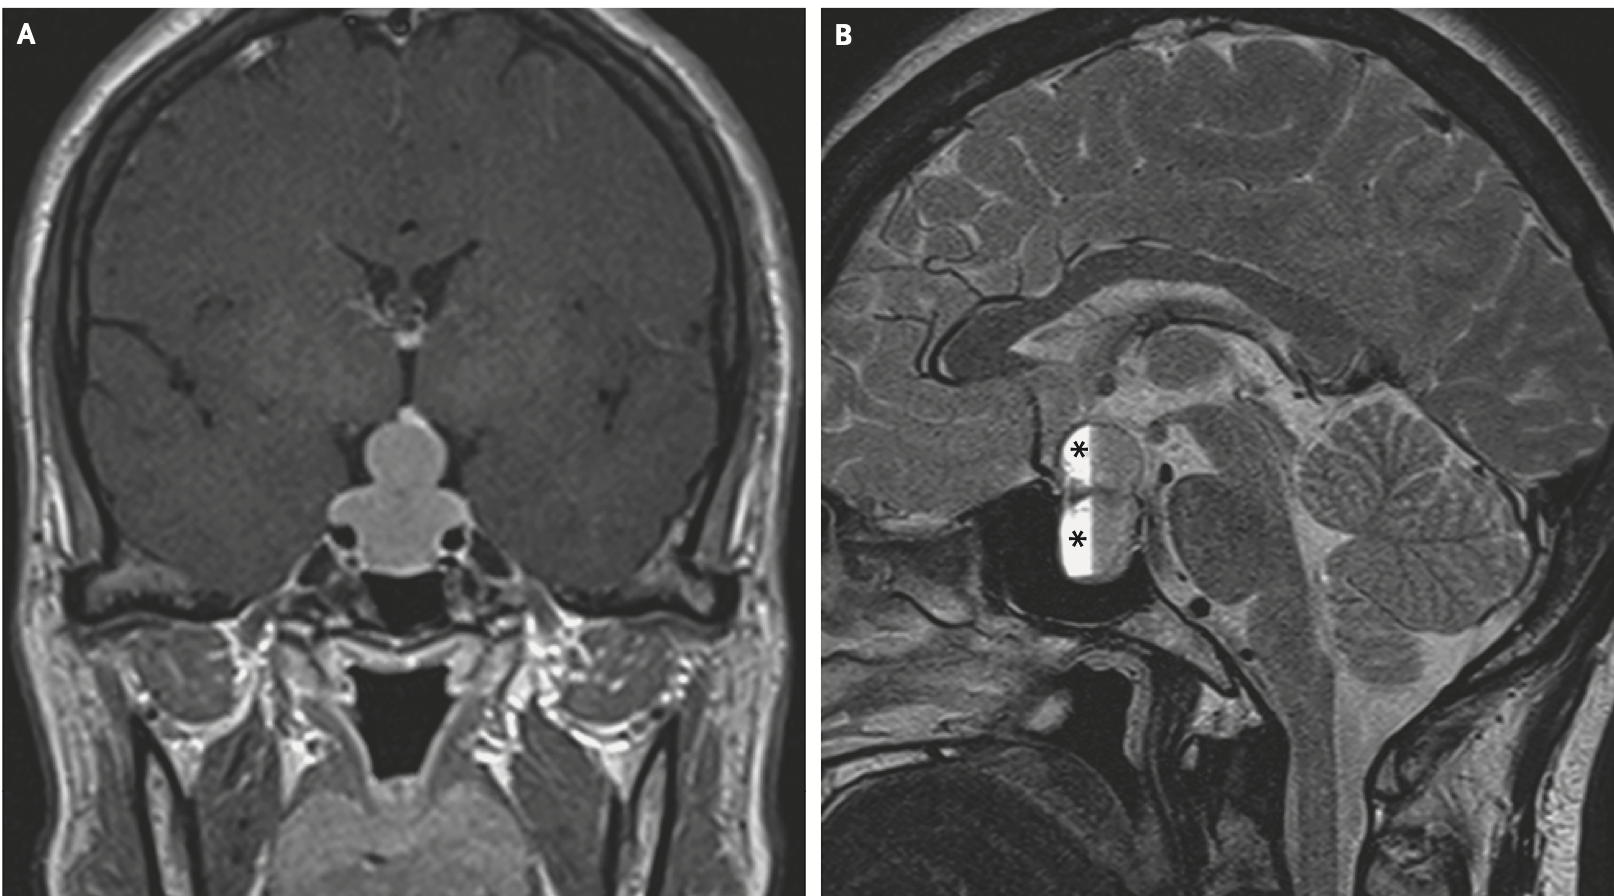

«Знак снеговика» указал на макроаденому гипофиза

Женщина, 47 лет, с жалобами на прогрессирующую головную боль, нечеткое зрение, галакторею и нарушения менструального цикла в течение последнего месяца. Острота зрения пациентки при осмотре составила около 0,4 (20/50 в американской системе), офтальмологической патологии не обнаружено. С помощью МРТ выявлено увеличение гипофиза с интрасупраселлярным ростом и сдавлением хиазмы (перекреста зрительных нервов). Также наблюдалось внутригипофизарное кровоизлияние.

На МРТ наблюдался «знак снеговика», возникающий при опухолях, медленно растущих вверх из турецкого седла. Лабораторные исследования подтвердили повышенный уровень пролактина в сыворотке крови (более 200 мг/мл), а также центральную надпочечниковую недостаточность и центральный гипотиреоз.